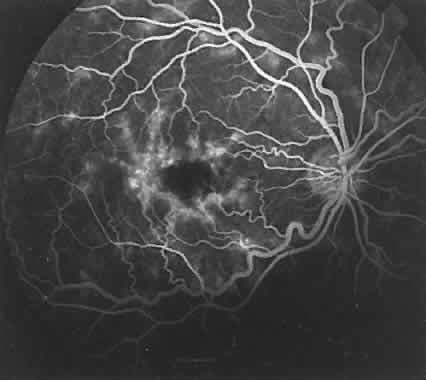

Fluorescein enters the choroidal vascular system via the posterior ciliary arteries. In a very lightly pigmented fundus, these larger choroidal vessels can be seen to fill with fluorescein (Fig. 11). The flow is directed toward the choriocapillaris, the filling of which is called the background choroidal flush (Fig. 12A and B). Normally, this stage begins before the arterial phase of the retinal circulation. If a cilioretinal artery is present, it will fill at the same time (see Fig. 12C). The arm-to-retina circulation time varies, averaging 10 to 20 seconds. The filling of the choriocapillaris occurs in irregular patches, best seen in the posterior pole (see Fig. 12B).41,42

Fig. 11. Early filling of large and medium-sized choroidal arterioles. A. Filling of large and medium-sized choroidal arterioles with fluorescein (black dots). Fluorescein has not reached the level of the choriocapillaris at this stage. B. Filling of large and medium-sized choroidal arterioles (arrows) in earliest stage of fluorescein study.

Fig. 12. Early filling of choriocapillaris. A. Fluorescein (black dots) filling of choriocapillaris in a patchy manner from efferent side of the circulation. A few molecules of fluorescein are seen leaking into the extravascular tissue in the area of Bruch's membrane. B. Early, patchy filling of choriocapillaris (black arrows). Medium-sized and smaller arterioles are also seen leading to patches of choriocapillaris filled with fluorescein (white-edged arrows). C. Filling of cilioretinal artery at the same time as the choriocapillaris begins to fill with fluorescein.

Each patch appears to fill evenly and is the result of separate, irregular areas of choriocapillaris supplied by larger choroidal vessels at slightly different times. The background choroidal flush gradually intensifies and spreads anteriorly toward the ora serrata. The entire choroidal sequence is obscured in the foveomacular area because of the denser pigmentation in the overlying RPE, and possibly the increased amount of xanthophyll in the sensory retina (see Fig. 7).16 To observe the larger choroidal vessels fill with fluorescein, attention must be focused deep to the RPE very early in the study, before the choroidal flush quickly masks these feeding vessels (see Figs. 7, 11B, 12B, 13B, and 14B). As the fluorescein enters the intravascular system of the choroid, it immediately leaks into the extravascular space (see Fig. 12A). This leakage is related to the capillary fenestrations seen in the choriocapillaris. Leakage of fluorescein in the choroid is most intense directly below Bruch's membrane and in the inner choroidal layers (see Fig. 13A). Diffusion then occurs throughout the entire extravascular space to eventually involve the inner scleral fibers (see Fig. 14A). The concentration of fluorescein rapidly equilibrates throughout the inner choroidal layers in both the intravascular and extravascular compartments. The concentration in the extravascular stroma of the outer choroid is probably less. This occurs during the filling phases of the study, usually by the venous phase of the retinal circulation (see Fig. 14). As the study progresses, fluorescein continues to leak from the choroidal vessels. Concurrently, (the density of fluorescein within the vessels becomes less because of the extravascular leakage and dilution by equal distribution throughout the entire blood volume. Therefore, the concentration of fluorescein within the choroidal vessels rapidly becomes less than that in the extravascular choroidal tissue. This occurs in the inner choroidal layers first and can be recognized as the medium-sized choroidal vessels begin to appear as silhouettes against the more concentrated extravascular fluorescence (Fig. 15).